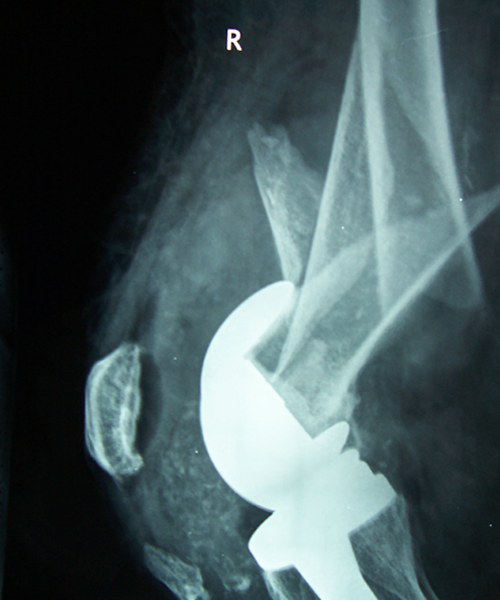

Case:14 Periprosthetic Fracture

60 years old patient with total knee replacement on left knee presented with open grade 1 injury. Debridement & slab given on emergency bases. Fixation with plate & screws done. Union was seen after 6 months.

Pre-Op AP

Pre-Op Lat.

Immdiate Post-op

1 and half months Post-op

2 and half months Post-op

3 and half months Post-op

4 and half months Lateral

6 Years Follow-Up